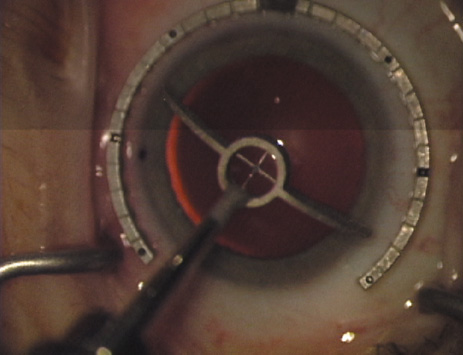

The extent of arc to be incised may be demarcated in several different ways. Our preferred method makes use of a modified Fine-Thornton fixation ring (Nichamin Fixation Ring and Gauge; Mastel Precision, Storz, Rhein Medical). This instrument serves to fixate and position the globe in order to optimize incision placement, as well as to delineate the extent of arc to be incised. One visually extrapolates from the limbus to marks on the surface of the ring. Each incremental mark is 10 degrees apart, and bold hash marks (180 degrees) opposite to each other serve to align and center the incision over the steep meridian. This approach obviates the need to ink and physically mark the cornea. If one desires, particularly when first gaining experience with LRIs, a two-cut RK marker may be used to place ink marks upon the cornea to show the exact extent of arc that is to be incised, in conjunction with the fixation ring/gauge (Fig. 4). Alternatively, various press-on markers are available, such as those made by Rhein Medical (Dell-Nichamin Marker, Nichamin-Kershner Marker, or the Ruminson Marker) (Fig. 5). ASICO and other instrument companies offer a full line of dedicated markers, rings, and blades for performing LRIs.

Fig. 4. The Nichamin Fixation Ring and Gauge serves to both fixate the globe and delineate the extent of arc to be incised; a two-cut radial marker may be used to mark the extent of arc to be incised, and the Mastel Nichamin Force AK Diamond Blade with preset depth of 600 microns.